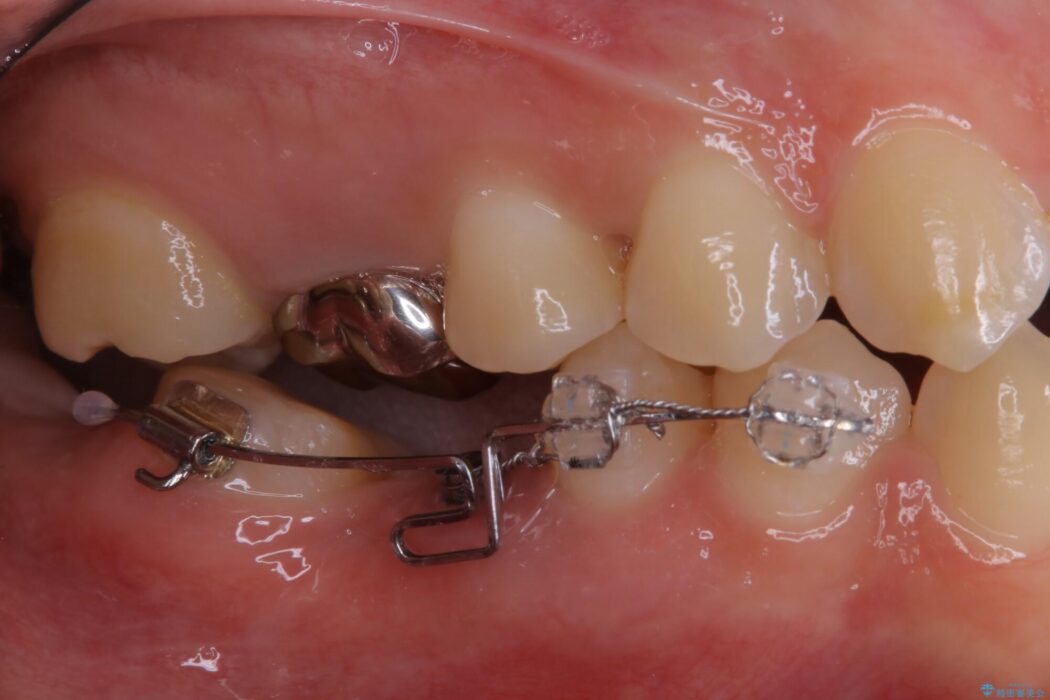

診査した結果、欠損した状態で長期間放置していたことが原因で最高峰の奥歯が欠けた部分に向かって傾斜してしまっていました。

この状態のままブリッジ治療へと進んでしまうと神経が露出する可能性が否定できないため、まずワイヤー装置による部分矯正で歯軸を通常位置へ戻してから補綴治療を行うこととしました。